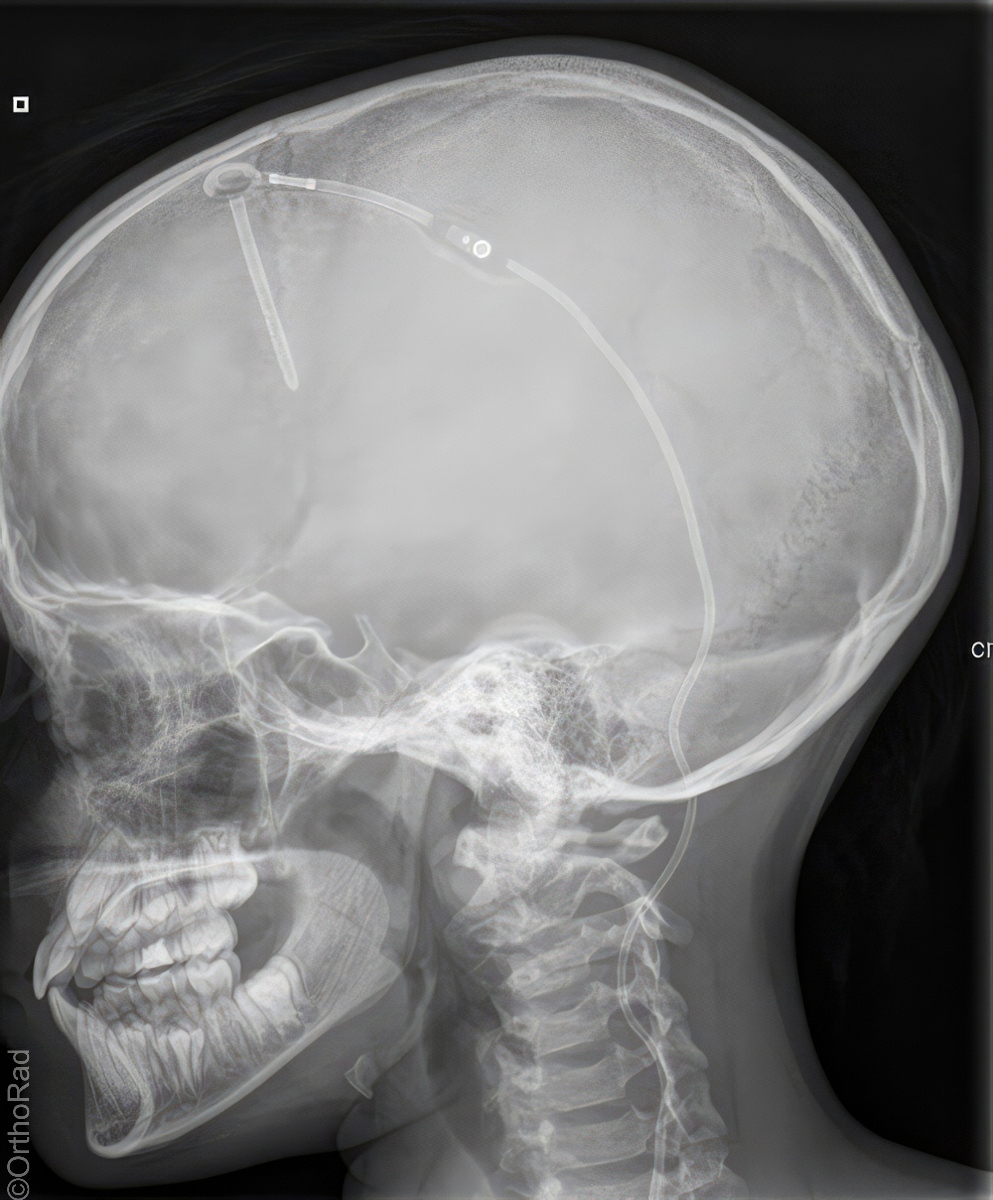

Shuntverlauf

Shuntkontrolle

1. Schädel/HWS ap

Patient in Rückenlage, Kinn anziehen lassen, 15° Keil unter den Kopf, so dass Deutsche Horizontale (DH = Frankfurter) senkrecht zum Film steht, Kopf muss seitengleich, symmetrisch gelagert werden.

2. Schädel/HWS seitlich

Patient in Rückenlage, Kopf auf die rechte Seite drehen und Medianebene verläuft parallel zum Tisch, Stirn-Augenbrauen-Linie verläuft senkrecht und die Stirn-Kinn-Punkte verlaufen parallel zur Filmeinblendung. Der Körper dreht sich somit etwas auf die rechte Seite.

3. Thorax/Abdomen

Patient in Rückenlage, Arme am Körper entlang, Beine geschlossen.

4. evtl Becken

Patient in Rückenlage, Beine leicht gespreizt.

Senkrecht auf Objekt, vom Schädel bis Abdomen müssen alle Bilder überlappend sein.

Anmerkung

Die Stelle (Narbe) an der der Shunt in dem Abdomen verschwindet, muss mit einer Metallkugel etc. markiert werden.